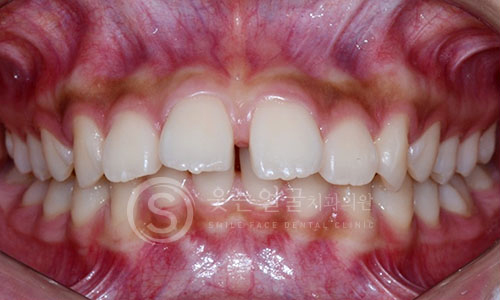

한눈에 보는

치아교정 전후사진